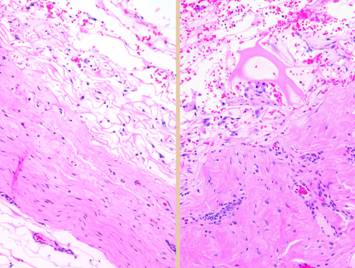

Left upper, the forearm contracture shown in a previous panel.  Integra was used to reconstruct skin after first excising the contracted scar.  Late results show no scar, no scar hypertrophy, no contractures.  Left lower, a keloid excised from behind the ear, skin then reconstructed preemptively with Integra to prevent recurrent keloid.  Late photo shows the area healed with no signs of scar hypertrophy.  Right, a pane of comparative histology.  Top row shows normal dermis, one view having been cut parallel to skin tension lines, the other orthogonal.  Whether seen on side or on end, normal dermis with normal elasticity and has an architecture of collagen bundles separated or porated with interstitial spaces which give it some deformability and pliability, typically greater in one direction than the other.  Middle row shows young scar and young Integra.  The scar is dense in collagen, no spaces, no opportunities for shifting and rolling of bundles, all oriented into locally thick bands but without an overall uniform direction, making the scar anisotropically stiff.  In comparison, young Integra has local fibrous foci which are separated from each other by the matrix, thereby maintaining interstitial porosity and the ability of domains to shift or distend relative to each other, a configuration and mechanics much more like normal dermis.  Bottom row shows scar and Integra in phases of late maturation after many years.  Both have remodeled away from their original appearance back toward normal dermis or fascia,  The difference is that young scar quickly becomes packed with immobile excessively dense collagen, and then it takes years to remodel back to normal stromal density, architecture, and mechanics.  Integra-CGM also takes years to remodel back to a strictly normal appearance, but it has the fundamental architectural and mechanical features of normal dermis right from the very beginning.

Left, a microscope image of normal wound healing.  The structure shown here is the prototypical wound.  Details of the structure and process will be explained in following panels.  Right, the microscopic appearance of fully regenerated Integra-CG matrix, the details likewise to be explained in following panels.  Even without explaining or focusing on specific details, the dissimilarity of the two can be appreciated.  Angiocytes and fibroblasts, vessels and connectives – that is all there is to these two tissues.  However, by supplying different “rules” or “subroutines” for the interaction and assembly of these elements, two different biomaterials emerge.  The rules or routines are based on the circumstances, reaction-to-injury versus embryonic regeneration.  The results have very different physical properties and implications for daily life, functional adaptations, and potential need for ongoing medical care.

Pictured is matrix regeneration within a piece of Integra collagen-gag matrix.  It is no longer the non-living empty matrix placed on the original wound, but a fully restored living material.  The details of this process are now presented.  However, even without knowing the specific details, it can be appreciated that the structure, morphology, and patterns of this regenerated biological material are different than the microscopic structure of the normal post-inflammatory wound.  Normal wound healing is triggered by inflammation and then evolves according to its own “program” of how angiocytes and fibroblasts rebuild a stroma of blood vessels and connective mesh.  Integra suppresses inflammation, and thus the normal “wound healing program” is never turned on.  Integra “heals” by a fundamentally different mechanism analogous to embryonic tissue generation.  Its build to a state of complete regeneration is uniform throughout the matrix, distributed rather than stratified, and when complete, it has created a new material that has characteristics mostly like normal dermis and quite unlike scar.  The matrix coaxes the same two cells, angiocytes and fibroblasts, to make a new tissue of blood vessels and connective mesh in a patterned morphology that is profoundly different then scar.  The same cells, making the same elemental components, assemble them in a completely different pattern than wound healing and scar because the embryogenesis-and-stromal-generation “program” is entirely different than the healing-and-scar “program”.